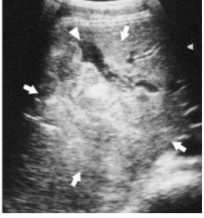

Từ những năm 1980, siêu âm được sử dụng rộng rãi ở Pháp, các nước Châu Âu và Nhật Bản để chẩn đoán chấn thương bụng [2]. Tại Việt Nam và nước phát triển như Pháp, Mỹ thì khám xét đầu tiên cần làm cho bệnh nhân chấn thương bụng kín là siêu âm [8]. Trên siêu âm hình ảnh tổn thương gan có thể gặp: Tụ máu dưới bao gan, đụng dập nhu mô gan, đường vỡ gan, dịch tự do trong ổ bụng. Ngoài ra siêu âm còn giúp đánh giá những tiến triển của tổn thương đụng dập, tụ máu đối với các trường hợp điều trị bảo tồn [14]. Hình ảnh đụng dập tổ chức được thể hiện bằng vùng tăng âm không đồng nhất trong mu mô gan, hình máu tụ trong nhu mô biểu hiện bằng vùng trống âm, hoặc có thể có máu tụ bên trong nhu mô gan đụng dập (biểu hiện bằng hình tăng âm bên trong hình trống âm). Đường vỡ gan được xác định bằng đường trống âm trong tổ chức, tuy nhiên đường vỡ khó xác định do bị máu cục che lấp.

Hình 1.6: Tụ máu trong nhu mô thùy gan phải (mũi tên).

Nguồn: Sato M., Yoshii H (2004) [15].